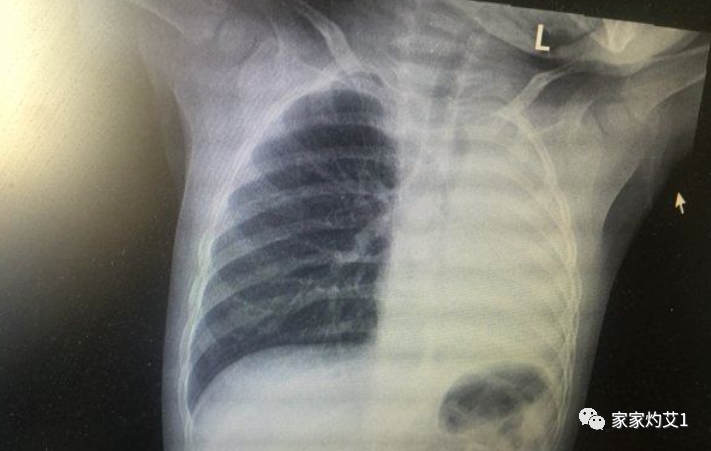

近日,一名12岁男孩咳嗽一周不就医,一侧肺部“扛”成了“白肺”。“抱着侥幸心理一直在家硬‘扛’,没想到‘扛’出这么重的病!”孩子家长悔不当初!

一下子,白肺成为了大家都在关心的问题。这几天又有一位12岁的男孩也因为感染后发烧、咳嗽,后来在医院检查出来了【白肺】。那么,到底什么是【白肺】呢?

白肺,并不是指肺变成了白色,白肺是肺部影像学表现的一个口语化描述。

肺炎≠白肺。比较严重的肺炎,胸片上才会出现“白肺”,这种情况实际占比并不高。

肺部是由肺泡组成的,肺泡里面充满空气,进行CT或者X线检查的时候,射线穿过肺泡,影像表现是黑色区域,但是当肺泡里出现炎症或感染,有渗出液和炎性细胞的时候,肺泡就被这些渗出液和炎性细胞所填充,射线就穿不透,在影像学上出现白色区域。

并不是只要肺部出现了炎症就都叫白肺,一般来讲肺部炎症较重、渗出液较多,白色的影像区域面积达到70%—80%时,在临床上把它称为白肺。